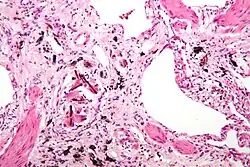

Asbestosis is the scarring of lung tissue (beginning around terminal bronchioles and alveolar ducts and extending into the alveolar walls) resulting from the inhalation of asbestos fibers. There are two types of fibers: amphibole (thin and straight) and serpentine (curly). All forms of asbestos fibers are responsible for human disease as they are able to penetrate deeply into the lungs. When such fibers reach the alveoli (air sacs) in the lung, where oxygen is transferred into the blood, the foreign bodies (asbestos fibers) cause the activation of the lungs' local immune system and provoke an inflammatory reaction dominated by lung macrophages that respond to chemotactic factors activated by the fibers.[20] This inflammatory reaction can be described as chronic rather than acute, with a slow ongoing progression of the immune system attempting to eliminate the foreign fibers. Macrophages phagocytose (ingest) the fibers and stimulate fibroblasts to deposit connective tissue.

Due to the asbestos fibers' natural resistance to digestion, some macrophages release inflammatory chemical signals, and other macrophages are killed, releasing reactive oxygen species and activating transcription factors, like NF-kB, which amplify the expression of pro-inflammatory cytokines.[21] These inflammatory chemical signals attract further lung macrophages and fibrolastic cells that synthesize fibrous scar tissue, which eventually becomes diffuse and can progress in heavily exposed individuals. This tissue can be seen microscopically soon after exposure in animal models. Some asbestos fibers become layered by an iron-containing proteinaceous material (ferruginous body) in cases of heavy exposure where about 10% of the fibers become coated. Most inhaled asbestos fibers remain uncoated. About 20% of the inhaled fibers are transported by cytoskeletal components of the alveolar epithelium to the interstitial compartment of the lung where they interact with macrophages and mesenchymal cells. The cytokines, transforming growth factor beta and tumor necrosis factor alpha, appear to play major roles in the development of scarring inasmuch as the process can be blocked in animal models by preventing the expression of the growth factors.[22][23] The result is fibrosis in the interstitial space, thus asbestosis.

This fibrotic scarring causes alveolar walls to thicken, which reduces elasticity and gas diffusion, reducing oxygen transfer to the blood as well as the removal of carbon dioxide. This can result in shortness of breath, a common symptom exhibited by individuals with asbestosis.[24] Those with asbestosis may be more vulnerable to tumor growth (mesothelioma), because asbestos decreases the cytotoxicity of natural killer cells and impairs the functioning of T helper cells, which detect abnormal cell growth.[25]

Extensive fibrosis of pleura and lung parenchyma -